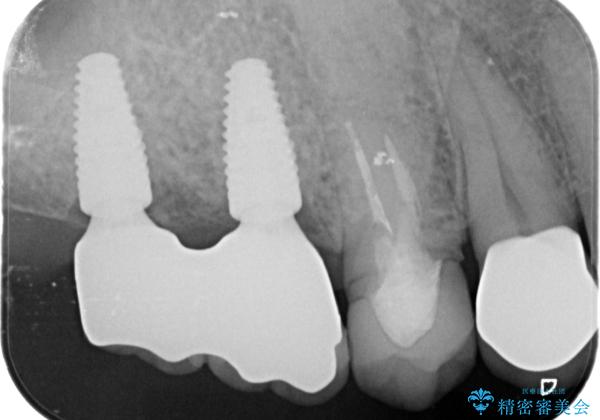

- 88万円(インプラント×2・仮歯×2・チタンカスタムアバットメント×2・ジルコニアクラウン×2)費用は治療当時の料金となります

人工歯根であるインプラントを埋入することで奥歯でまたしっかりと噛める咬合機能を回復します。